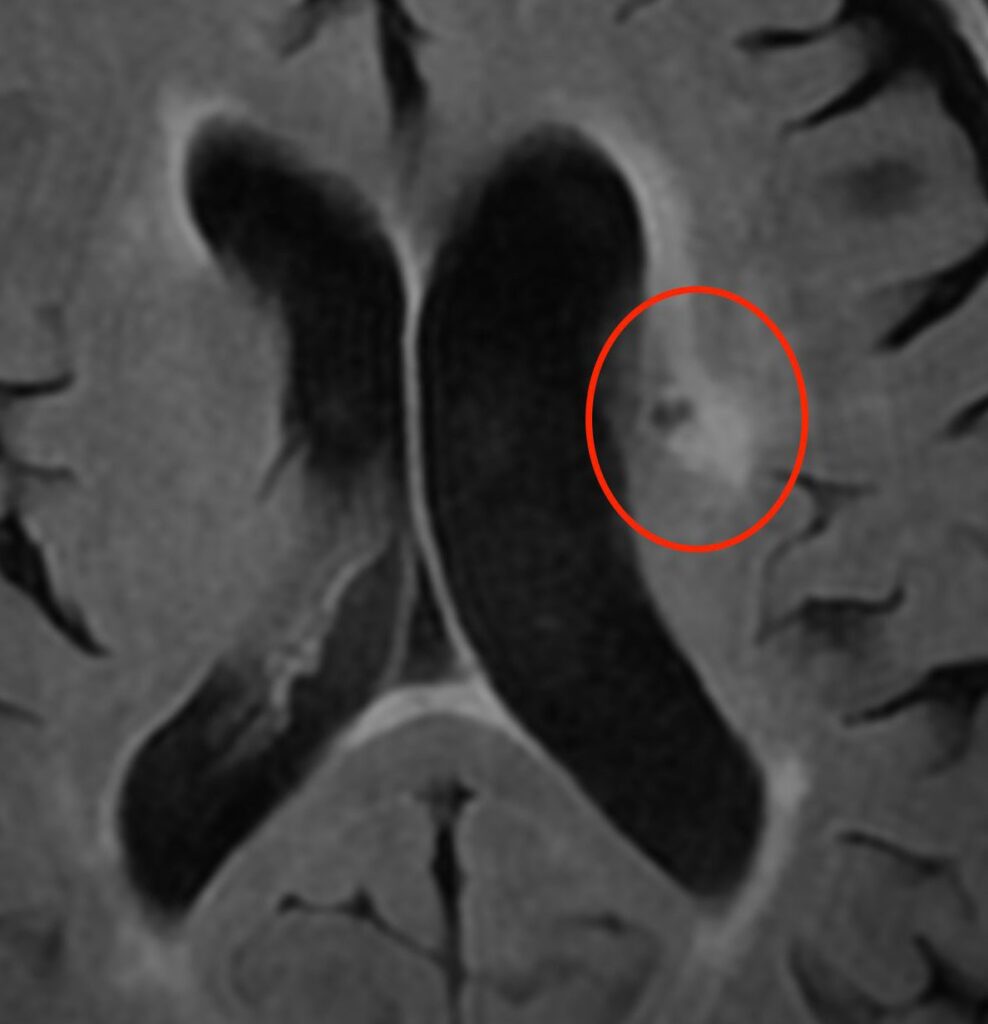

微小脳梗塞

高血圧や糖尿病が原因で脳の細い動脈が詰まって生じます。

微小脳出血

高血圧が原因で脳の細い動脈が破綻して生じます。